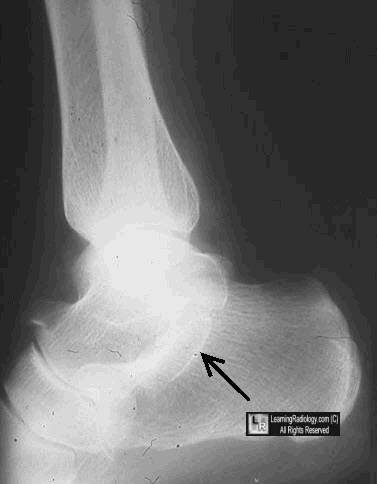

The Anteater Nose Sign

Tarsal coalition is a congenital malforma-tion of the foot, thought to be the result of embryonic failure of tarsal segmentation and resulting in abnormal osseous, carti-laginous, or fibrous communication be-tween bones within the hindfoot or mid- ... Retrieve Document